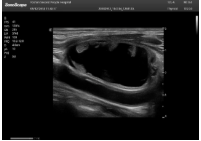

肝癌

2相控陣探頭

探頭面是平面,接觸面小,近場視野最小,遠場視野大,成像視野呈扇形,適用于心臟。

心臟探頭通常按應(yīng)用人群劃分為成人、兒童、新生兒三類:(1)成人心臟位置最深、搏動速度慢;(2)新生兒心臟位置較淺、搏動速度最快;(3)兒童心臟的情況介于新生兒與成人之間。

肥厚性心肌病-心尖四腔